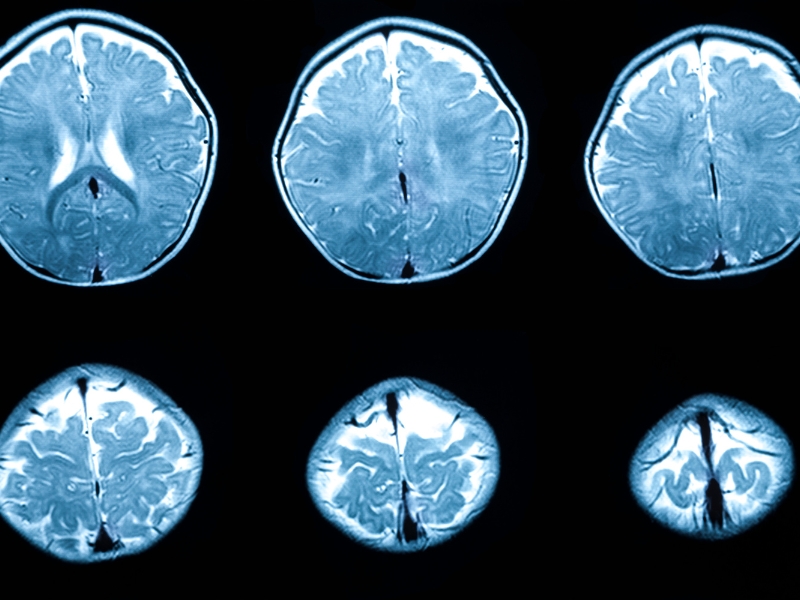

Thoái hóa chất trắng là gì?

Thoái hóa chất trắng là tình trạng tổn thương ở chất trắng, thành phần cấu tạo nên phần lớn hệ thần kinh trung ương. Chất trắng chứa các sợi thần kinh có bao myelin bao phủ, giúp tăng tốc độ và hiệu quả của việc truyền tín hiệu trong não bộ. Khi thoái hóa xảy ra, bao myelin bị hư hại, làm giảm khả năng truyền tín hiệu và gây ra nhiều vấn đề về nhận thức, vận động và cảm giác.